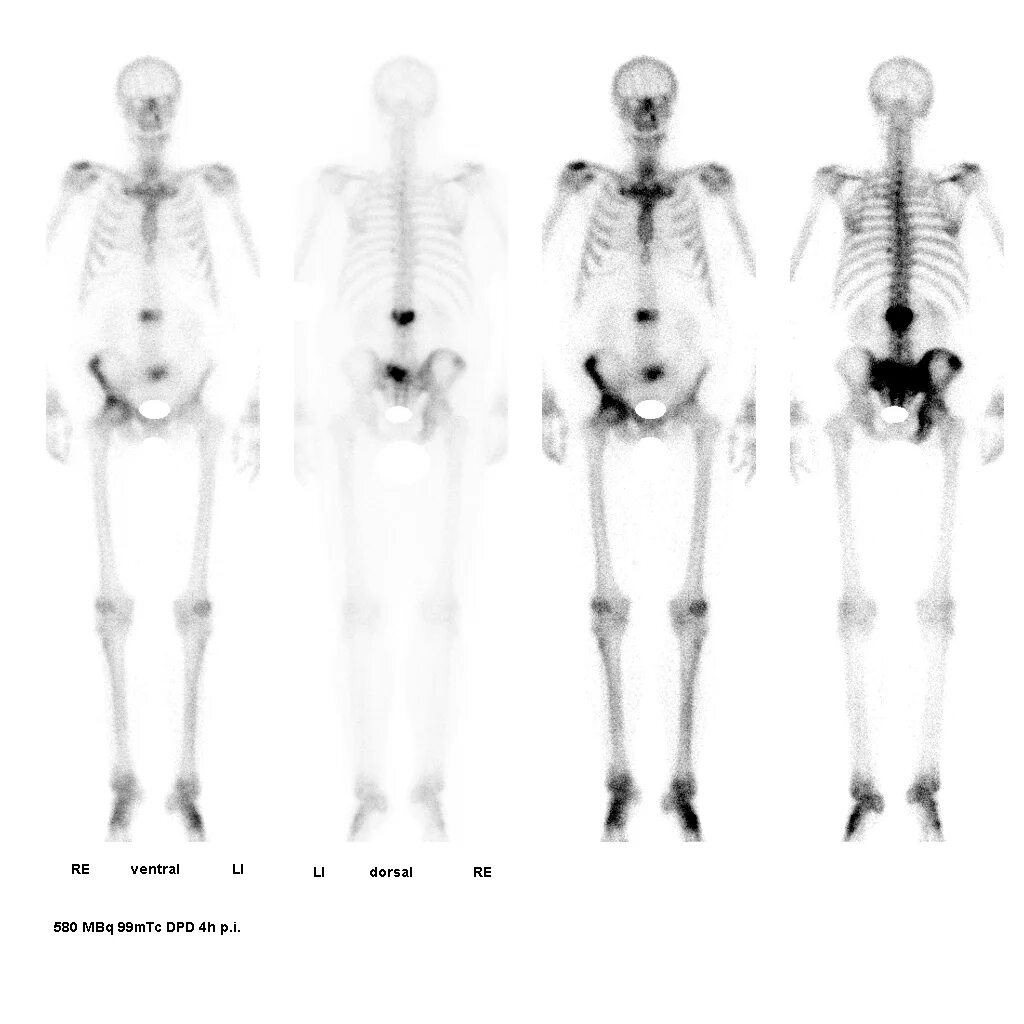

Химиотерапия при метастазах в костях